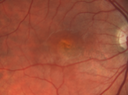

29 year old female reports that the right eye became blurry with a "funny feeling" about a weeks ago which has progressed to central grey spot. History of PCOS, Endometriosis, possibly Fibromyalgia. 1 healthy 2 year with unremarkable pregnancy. No pain OD except on the first day the patient noticed decreased. Patient had flu-like symptoms after Thanksgiving 2017 and went to Urgent Care in AZ after she became worse. Has taken amoxicillin antibiotic since Urgent Care visit 11/30/17. Patient had rashes on hands and feet as well as chest. Felt she had "little cuts" on hands and feet. VA 20/200 OD, 20/32 OS. Vision in the right eye improved to near normal within 1 months and elevated titers of Coxsackie B3 and B4 titers.

UAI-color_28229.png

Unilteral Acute Idiopathic Maculopathy - Initial Presentation404 views00000

UAI-color_28129.png

Unilteral Acute Idiopathic Maculopathy - Initial Presentation400 views00000

UAI-color_28329.png

Unilteral Acute Idiopathic Maculopathy - Initial Presentation424 views00000

uaim-2_weekslater.png

Unilteral Acute Idiopathic Maculopathy - 2 weeks following other images454 views00000